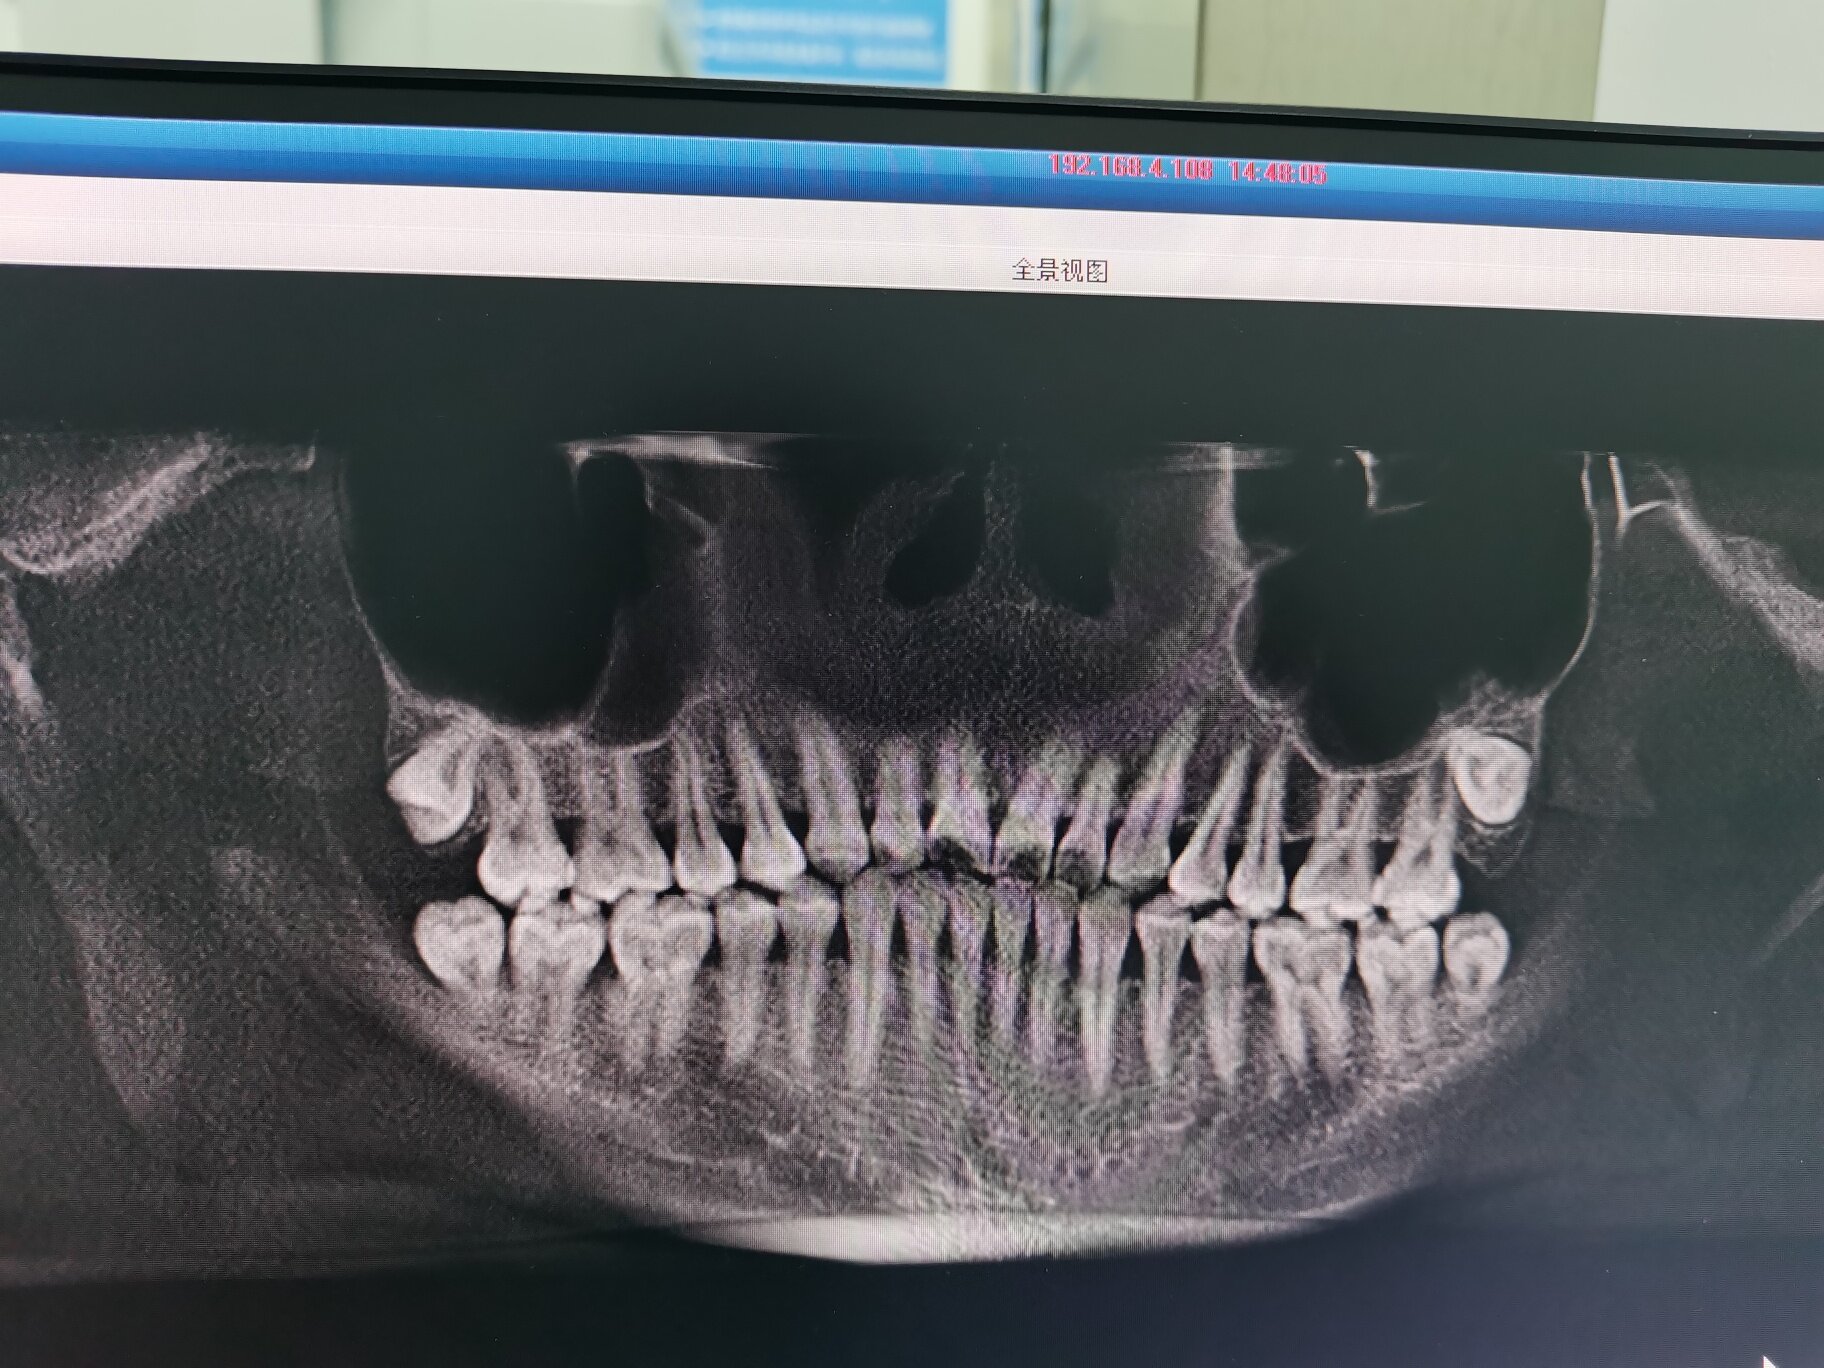

智齿是根据拔的难度来收费的,你把拍的片子发出来看有没有懂的人回复你

拔的左下边一颗,有懂的吗